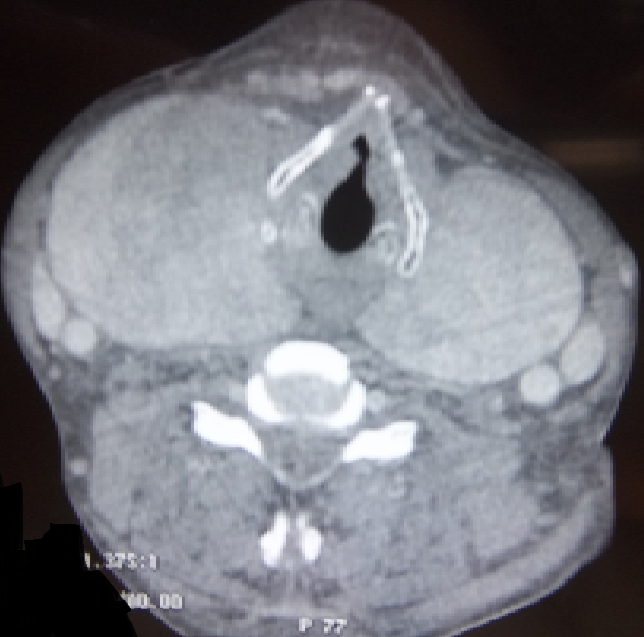

L'amylose se caractérise par un dépôt extracellulaire anormal de fibrilles amyloïdes dans les différents tissus. L'apparition d'un goitre secondaire à l'infiltration amyloïde est rare. Il est exceptionnellement révélateur d'une amylose systémique. Son diagnostic est histologique. Patient âgé de 45 ans, aux antécédents de tuberculose pulmonaire traitée et suivi pour une maladie de Crohn, a consulté pour une tuméfaction cervicale antérieure augmentant rapidement de volume et des signes de compression (dyspnée et dysphagie évoluant depuis un mois). L'examen physique a retrouvé un volumineux goitre homogène, ferme et indolore à la palpation. Les aires ganglionnaires étaient libres. L'échographie cervicale a objectivé un goitre homogène. La TDM cervico-thoracique a révélé un goitre homogène arrivant jusqu'à l'orifice supérieur du médiastin avec compression de la filière pharyngo-oesophagienne. Le bilan hormonal thyroïdien était normal. Plusieurs diagnostic ont été évoqués notamment un lymphome ou un carcinome thyroïdien. Le patient a bénéficié d'une thyroïdectomie totale. L'examen anatomopathologique a montré la présence de quelques vésicules thyroïdiennes noyées dans de larges plages éosinophiles amorphes ayant une biréfringence jaune-verdâtre après coloration au rouge Congo en lumière polarisée caractérisant le goitre amyloïde. L'examen immuno-histochimique a conclut à une amylose de type AA. Une recherche systématique d'autres localisations amyloïdes a objectivé une localisation salivaire avec une biopsie de glandes salivaires accessoires positive. Un traitement hormonal substitutif lui a été instauré.